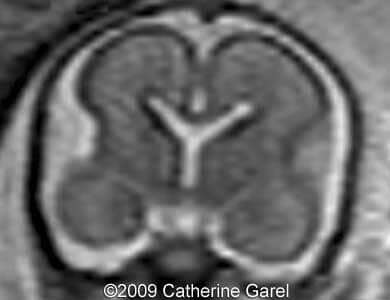

Images 7,8: MRI Image 7 shows a wavy midline structure which was detected on the ultrasound images (Images 4,6), the structure is hypodense on the MRI images. Image 8 shows an interhemispheric fissure in the anterior and posterior region.

Case262_7

Case262_8

Images 9,10: Images 9, 10 show a fusion in the posterior frontal and parietal regions, indicated by arrows.

Case262_9a

Case262_10a